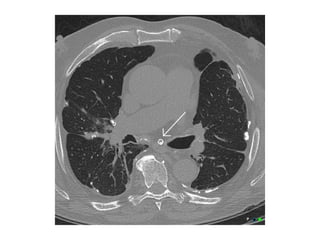

73-year-old woman with Sjogren syndrome symptoms, including dyspnea and

arthralgias, and biopsy-proven lymphoid interstitial pneumonia (LIP),

contrast-enhanced coronal reformatted image through lungs shows

numerous thin-walled cysts mostly located adjacent to blood vessels, these

perivascular cysts are identified in most patients with LIP